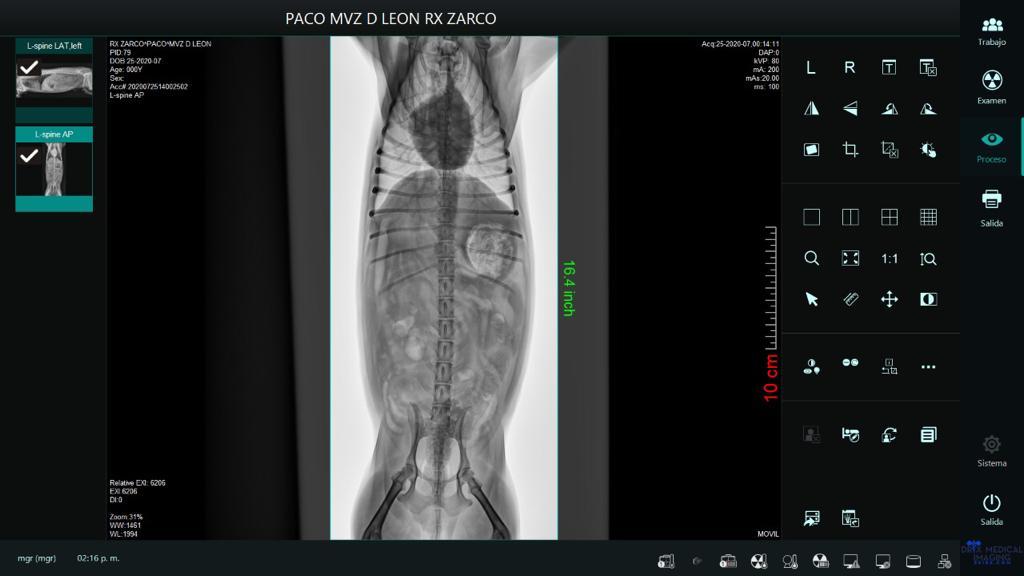

Paciente: Pako

Raza: Yorkshire

Padecimiento: Síndrome de Woobler

Paciente presentado con inicio con dolor intenso de cuello que posteriormente se convierte en una descoordinación y parálisis desde el cuello hacia sus cuatro extremidades.

En la radiografía se encuentra una compresión.

Tiempo de evolución 2 meses.

Tratamiento: 2 sesiones de PRP ozonizado más CTM (10 millones) vía paravertebral